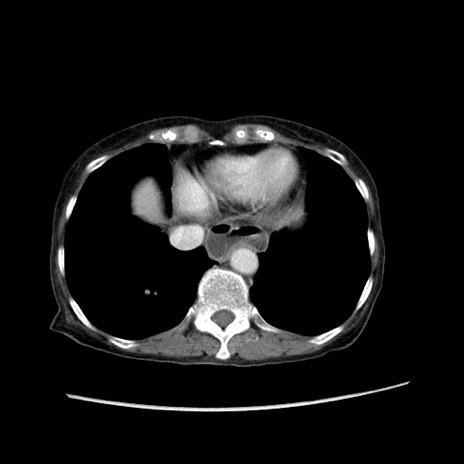

症例25(横断像)

【症例】80歳代女性

【主訴】胸のつかえ感

【現病歴】約9時間前に食後から胸のつかえた感じあり、嘔吐あり、来院。

【既往歴】胃癌(全摘)、胆摘、虫垂炎

【身体所見】心窩部に圧痛あり、反跳痛なし。

【データ】WBC 5700、CRP 0.05